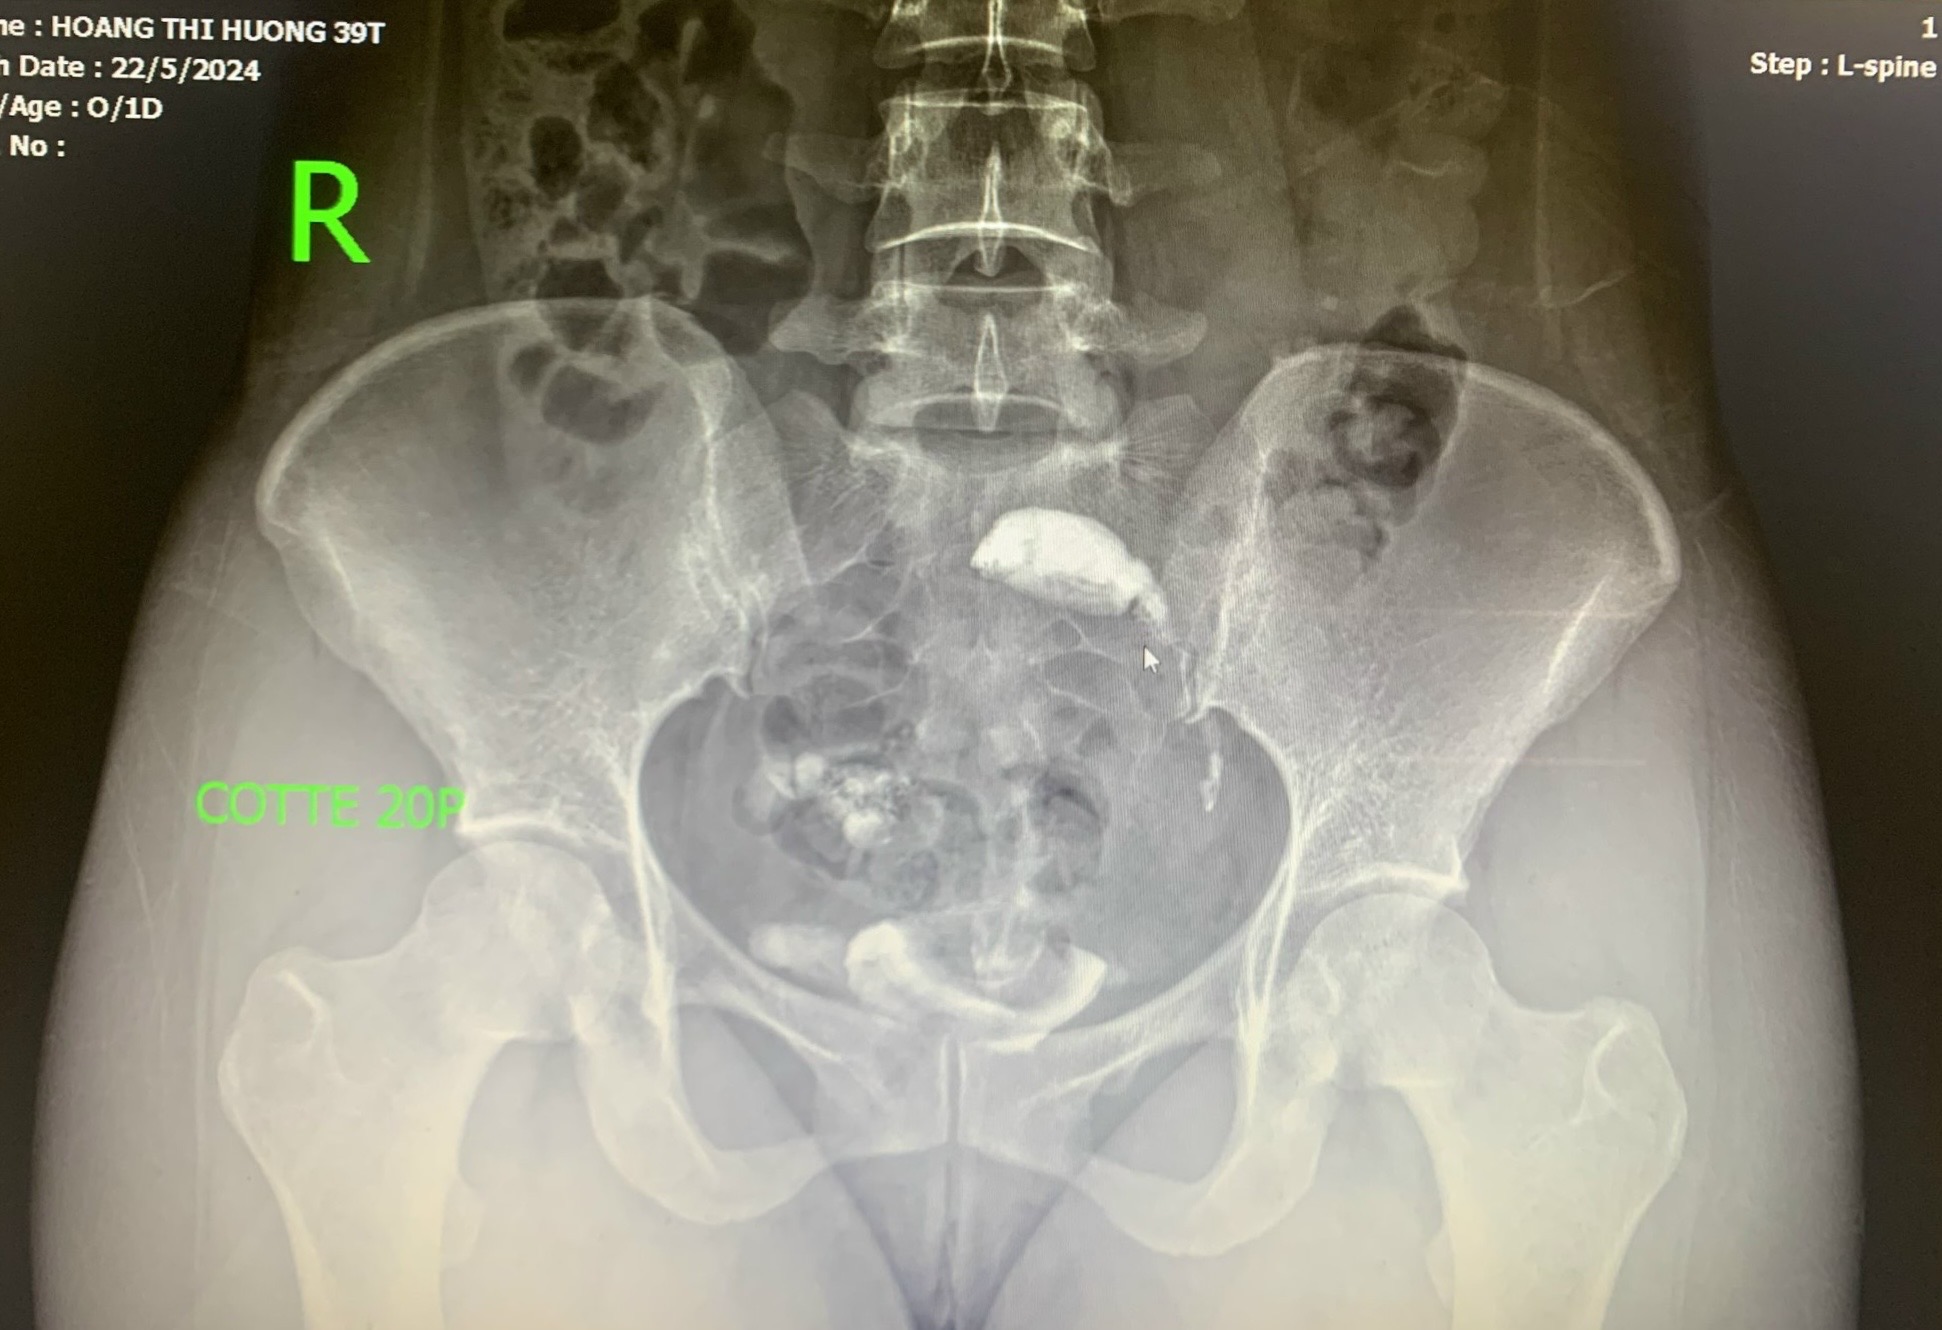

Hình ảnh chụp X-quang tử cung vòi trứng

Bác sĩ Bệnh viện Đa khoa Yên Bình Thái Nguyên đang thực hiện kỹ thuật chụp X-quang tử cung vòi trứng